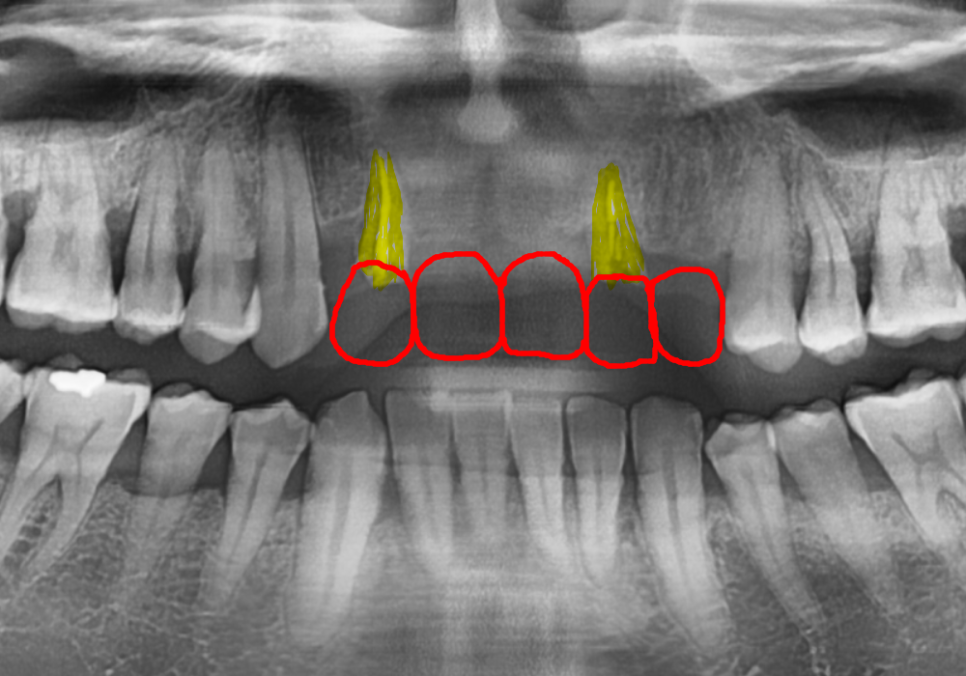

브릿지를 지탱하던 치아 2개(#12, #22)가

잇몸 안에서 완전히 부러져

뿌리만 간신히 남아있는 상태였습니다.

지금 남아있는 뿌리는 단 두 개인데,

이 약해진 기둥 두 개가

다섯 개의 치아(#12, 11, 21, 22, 23)가 받는

엄청난 하중을 전부 견뎌내기에는

사실상 한계가 있었습니다.